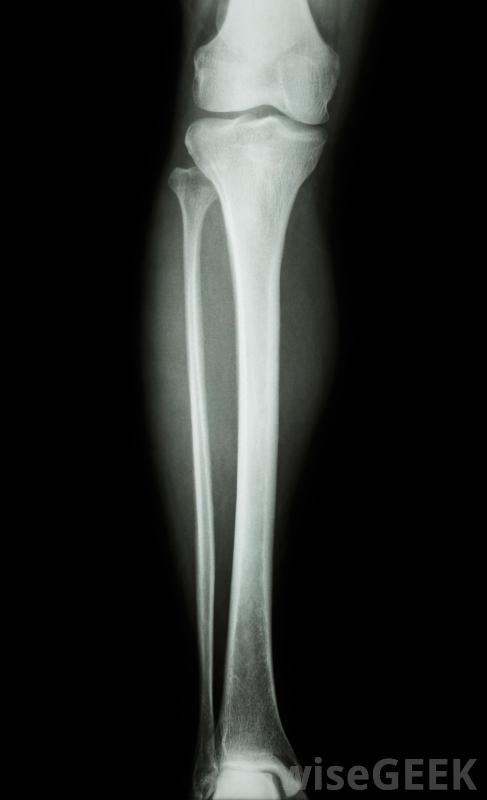

股骨釘是一種外科技術,用于治療骨折或骨折的股骨,或股骨。該過程包括將一根稱為髓內釘或股骨釘的金屬棒插入股骨,并對其進行定位,使其沿著骨干的長度垂直運行。當釘穿過骨頭的中部時,它起到將兩個骨折段固定在一起,上下可放...

股骨釘是一種外科技術,用于治療骨折或骨折的股骨,或股骨。該過程包括將一根稱為髓內釘或股骨釘的金屬棒插入股骨,并對其進行定位,使其沿著骨干的長度垂直運行。當釘穿過骨頭的中部時,它起到將兩個骨折段固定在一起,上下可放置螺絲釘固定,防止骨頭繞棒旋轉,與夾板或石膏相比,這種方法的優點是使股骨骨折迅速穩定,患者活動更快,避免長期不活動的并發癥,例如腿部的血塊。

股骨是人體內最難折斷的骨頭。